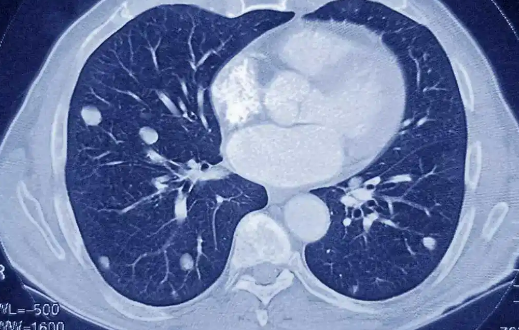

两肺多发小结节是一种影像学的描述,通常是在胸部CT检查时发现两肺有高密度的肺部小结节形成,它可以由良性的病因引起,亦可以见于某些恶性肿瘤,例如可以由细菌、真菌、结核分枝杆菌感染引起两肺多发小结节,特别是粟粒型肺结核患者两肺可以出现弥漫性的小结节影。

两肺多发小结节当然还可以见于其它良性病因引起,例如某些陈旧性病灶,特别是钙化灶,部分良性肿瘤也可以引起。还要注意排外是否有恶性肿瘤引起的两肺多发小结节,特别是肺癌以及肺内转移癌等,对于由恶性肿瘤引起两肺多发小结节的患者其预后不良。